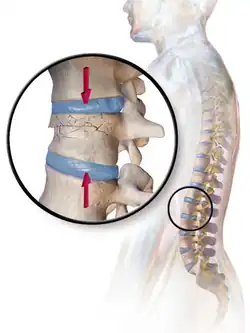

• Compression fracture/wedge fracture – usually occurs in the vertebrae, for example when the front portion of a vertebra in the spine collapses due to osteoporosis (a medical condition which causes bones to become brittle and susceptible to fracture, with or without trauma)

Compression fracture/wedge fracture Usually occurs in the vertebrae, for example, when the front portion of a vertebra in the spine collapses due to osteoporosis (a medical condition which causes bones to become brittle and susceptible to fracture, with or without trauma)